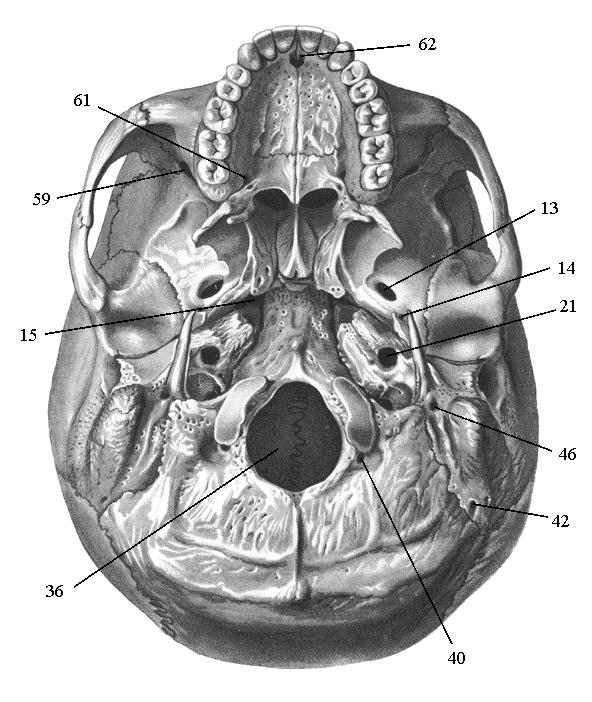

Анатомические детали: Фотографии топографии черепа с нижнего вида

Раздел: Альбом идей